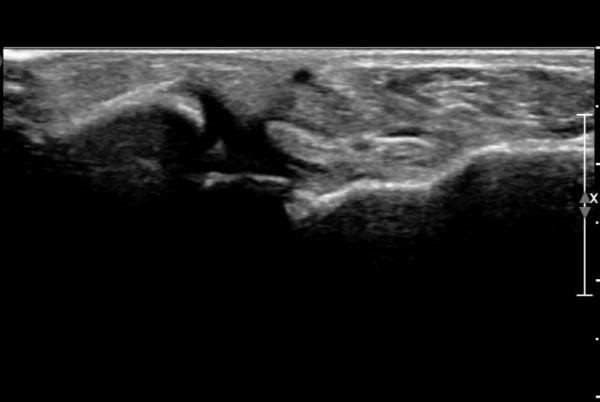

ÃÊÀ½ÆÄ ¼Ò°ß :  ¹ß¸ñ ¾Õ Á¾´Ü¸é°Ë»ç¿¡¼­ ¹ß¸ñ°üÀý³»  ¾à°£ÀÇ ¼ö¾×Àú·ù°¡ °üÂûµÊ(»çÁø 1).